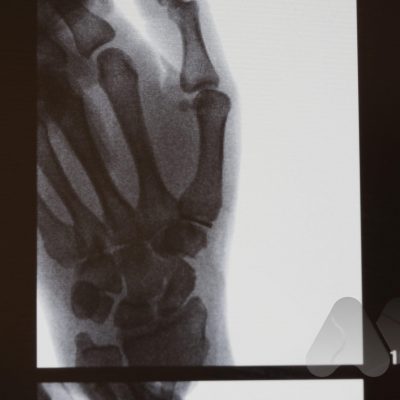

Arthritis can affect any joint in the body. The most common types of arthritis include osteoarthritis, rheumatoid arthritis and post-traumatic arthritis. Osteoarthritis is a degenerative joint disease where the smooth cartilage covering the bone ends, wear out, causing pain, swelling and stiffness and in the hand commonly affects the PIP joint, DIP joint and base of thumb (CMC joint). It commonly occurs in older people.

Common symptoms cause pain, and stiffness in the small joints of the hand. The knuckles can become swollen or show bumps and bony nodules called Heberden’s or Bouchard’s nodes in the fingers. Base of thumb arthritis can sometimes lead to the thumb being drawn into the palm and loss of a wide hand span. People often complain of difficulty opening jars and taps. X-Rays are often the most simple and effective way of showing arthritis.